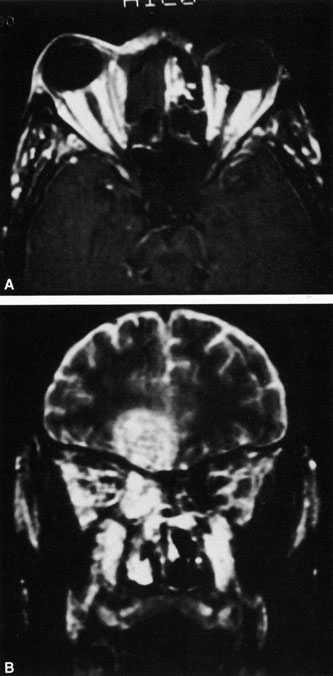

Fig. 18. Orbital abscess. A. Computed tomography of an orbital abscess presenting as an enhancing intraconal mass on right side. B. T1-weighted image. C. T2-weighted image. Note area of high signal corresponding to abscess.

Magnetic resonance imaging (MRI) is purported to be more useful than CT in the diagnosis of preseptal cellulitis. It is less reliable at diagnosing the subtle signs of muscle enlargement and periscleritis and thus is not as useful in differentiating orbital cellulitis from other inflammatory orbital diseases.71 On MRI with gadolinium contrast, orbital cellulitis may show a smearing or linear streaking of the normal fat shadows on T2-weighted images. MRI is excellent for demonstrating localized fluid collections such as abscesses. It is not helpful in distinguishing a transudate from an exudate, because both appear liquid and are of low intensity on T1-weighted images and bright on T2-weighted images (Fig. 19).